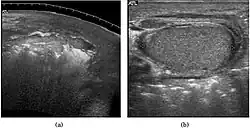

Fig. 3. Seminoma. (a) Seminoma usually presents as a homogeneous hypoechoic nodule confined within the tunica albuginea. (b) Sonography shows a large heterogeneous mass occupying nearly the whole testis but still confined within the tunica albuginea, it is rare for seminoma to invade to peritesticular structures.

Approximately 95% of malignant testicular tumors are germ cell tumors, of which seminoma is the most common. It accounts for 35%–50% of all germ cell tumors. Seminomas occur in a slightly older age group when compared with other nonseminomatous tumor, with a peak incidence in the fourth and fifth decades. They are less aggressive than other testicular tumors and usually confined within the tunica albuginea at presentation. Seminomas are associated with the best prognosis of the germ cell tumors because of their high sensitivity to radiation and chemotherapy.

Seminoma is the most common tumor type in cryptorchid testes. The risk of developing a seminoma is increased in patients with cryptorchidism, even after orchiopexy. There is an increased incidence of malignancy developing in the contralateral testis too, hence sonography is sometimes used to screen for an occult tumor in the remaining testis. On US images, seminomas are generally uniformly hypoechoic, larger tumors may be more heterogeneous [Fig. 3]. Seminomas are usually confined by the tunica albuginea and rarely extend to peritesticular structures. Lymphatic spread to retroperitoneal lymph nodes and hematogenous metastases to lung, brain, or both are evident in about 25% of patients at the time of presentation.